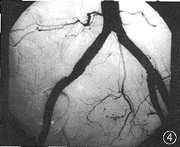

图4 覆膜支架术后,DSA示右髂总动脉管壁光整、通畅,管腔大小正常,原病变消失

手术经过:器械采用Boston 公司 Passeger 支架(直径1 cm,长度6 cm),为镍钛合金的温控记忆支架,由Cragg支架外覆一层人工血管制成。手术在Philips V3000型DSA机上进行,常规消毒铺巾,局麻下行左侧股动脉穿刺,并置入导管鞘,将 5 F Cobra导管选择性置于右侧髂内动脉(操作中避免损伤动脉瘤),先用弹簧圈(Boston)将右髂内动脉完全栓塞,再行右侧股动脉切开暴露,穿刺后置入血管鞘(Meadox-Passager introducer sheath),因考虑到所用Passeger支架推送装置为9 F直径,为避免穿刺后止血不佳,故采用小切口将右侧股动脉暴露,以便术后止血。做路径造影后在路径导引下达腹主动脉分叉处,再联接支架装置与管鞘,由推送导管(Pusher catheter)推顶支架至病变处,再释放 Passager支架,并予以球囊充分扩张。术后行造影,示右髂总动脉病变区消失,无内漏(图4)。